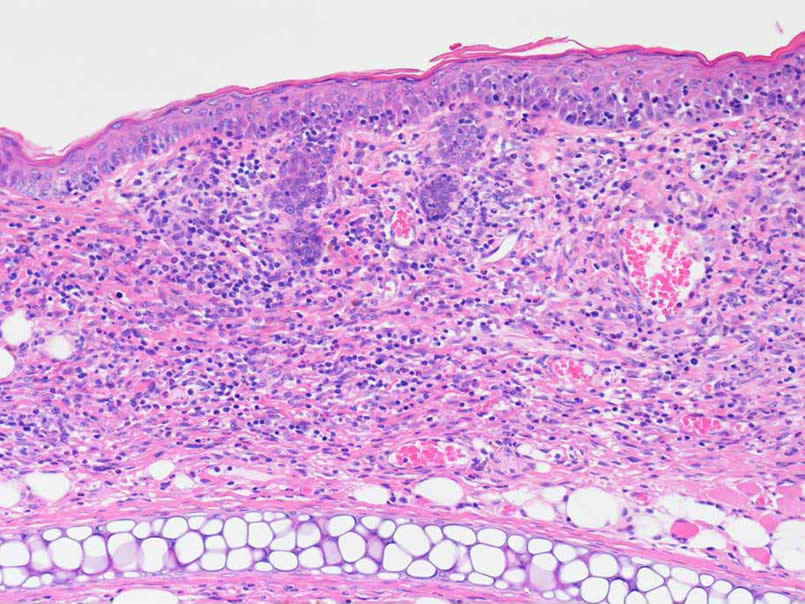

病理切片作为一种实验技术已广泛应用于科研、教学、病理检验等工作中,有较高的使用价值。实验的整个流程大致分为以下几个步骤:组织固定、包埋、切片、脱水、透明、封片、染色。病理切片的质量对病理诊断有一定影响。HE染色(苏木素—伊红染色)的情况与制作切片的每一个过程都有着紧密的联系,包括时间的控制,切片的厚度等,每一个小环节都会严重影响病灶的呈现。

2、样本为病理切片,提供染色完成的切片及详细的解读报告

3、样本为组织,提供石蜡块、病理染色切片以及详细的解读报告